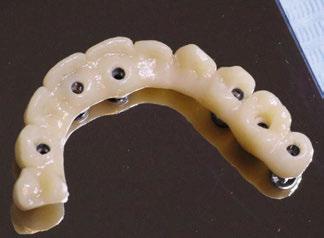

Presentamos el tratamiento rehabilitador de una paciente, realizado íntegramente en una sesión. Para este caso se ha utilizado un protocolo quirúrgico digital y guiado mediante la Plataforma de Planificación Bego Guide. Asimismo, se ha diseñado digitalmente una prótesis de carga inmediata atornillada e impresa con resina Bego VarseoSmile TriniQ®. Por lo tanto, se trata de un caso cuyo tratamiento precisa diferentes fases, pero efectuadas, todas ellas, el mismo día. De forma sencilla y cómoda para la paciente y el odontólogo, se ha obtenido una rehabilitación fija, funcional y estética. Palabras clave: Cirugía guiada, implantología oral guiada, cirugía sin colgajo, férula quirúrgica, rehabilitación fija maxilar, impresión digital, escáner intraoral, implantes dentales.

Dado que la estabilidad primaria se ha conseguido en la mayoría de los implantes, coincidiendo con la previsión propuesta en la planificación, procedemos ahora a la fase protésica. En el caso que nos ocupa, la paciente reside lejos, por lo tanto, colocamos tapones sobre los pilares transepiteliales y descansa en la sala de recuperación (Figura 30).

El procedimiento de diseño, impresión, pulido y cementación de aditamentos consume

Figura 34. Rehabilitación superior impresa en resina Bego VarseoSmile TriniQ® lista para atornillar. Se han anulado de la oclusión aquellos implantes que no obtuvieron una estabilidad primaria superior a 35 N/cm2 Figura 31. Escaneado intraoral postcirugía. Figura 32. Rehabilitación recién impresa a través de impresora Varseo XS con resina Bego VarseoSmile TriniQ®. Figura 33. Ajuste pasivo entre aditamentos protésicos y la rehabilitación impresa.

aproximadamente una hora y media. Usamos resina Bego VarseoSmile TriniQ® para puentes definitivos. Aunque en este caso la vamos a usar para confeccionar unas prótesis fijas atornilladas provisionales de larga duración, dado al aumento de dimensión vertical que vamos a realizar a la paciente, de esta forma obtendremos una neuroprogramación de la ATM reinstaurando una Dimensión Vertical apropiada y mejorando la estética facial de la paciente. Excluimos de la carga aquellos implantes que no obtuvieron una estabilidad primaria superior a 35 N/ cm2. El material permite la realización de una carga inmediata en material definitivo en puentes (Figuras 31 a 38).